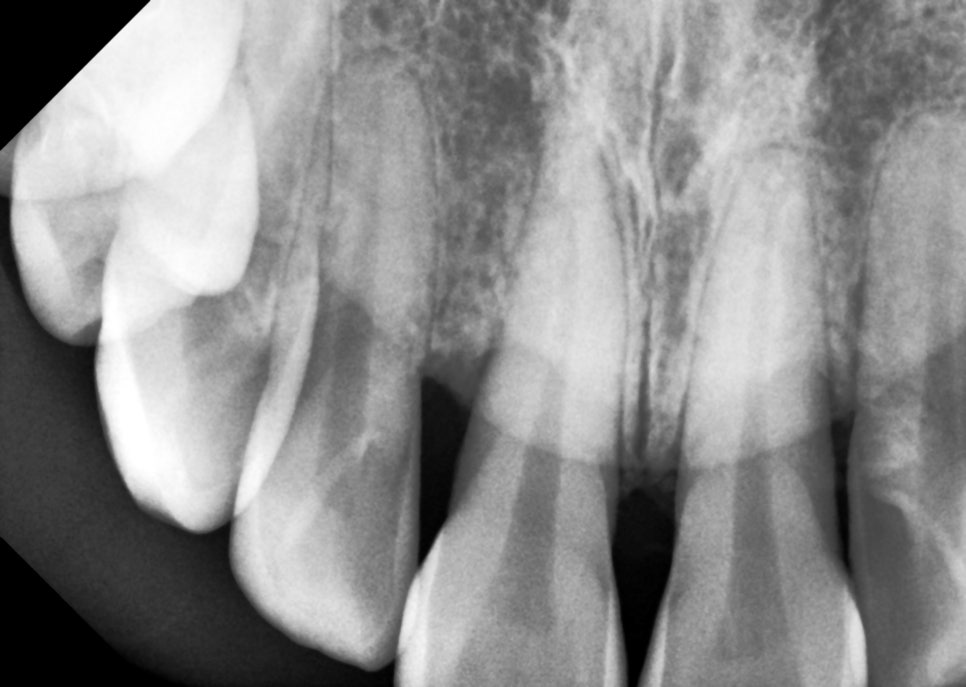

치석 제거 완.

그러면 이렇게 매~끈한 뿌리를 가질 수 있습니다.

만약 치석을 제거하지 않고

레진을 떼운다면 어떻게 됐을까요?

치석이 더 잘 쌓이게 되는 건 물론이고

치석 위에 레진을 쳐발쳐발하게 되면

당연히 레진과 치아 사이 접착이 실패하고

잇몸은 계속해서 안좋아지겠죠...

이렇게 예상되는 문제를

미리 제거하고 레진을 해야합니다.